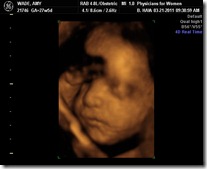

How Far Along: 26 weeks

Gender: We're having another little boy, Anderson Moore Wade.

What I am looking forward to: 4D ultrasound in two weeks!